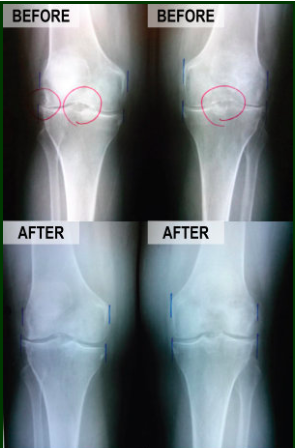

Scientific Advancements in Regenerative Medicine to Avoid Knee Surgery

Utilizing advancements in technology, scientists have discovered how to harness the human body’s natural ability to heal and direct those cells to stimulate regeneration of chronically injured tissues. These procedures are far less invasive than their surgical alternatives, resulting in significantly less pain following the procedure and far faster recovery times.

Utilizing the same technologies currently being used at major medical facilities such as the Mayo Clinic, Dr. Morales will remove and isolate the cells in your body responsible for stimulating the healing process prior to re-injecting them directly into your damaged tissues. All injections are performed with ultrasound or fluoroscopic (x-ray) guidance to assure precise localization of the injection into the exact location of the damage. The Regenerative Medicine procedures performed in our clinic are medically proven, with new studies being published monthly in major medical journals.